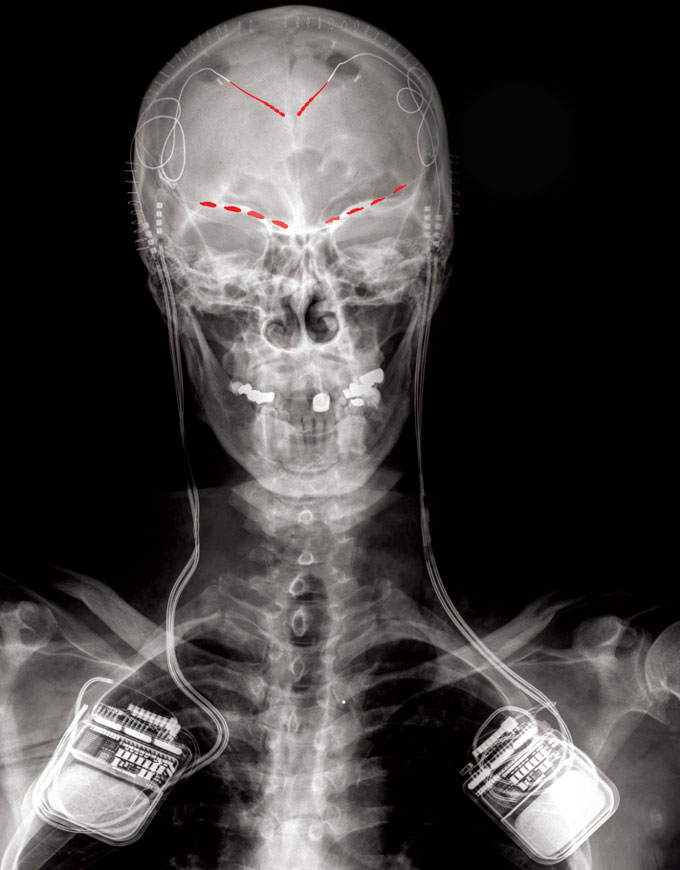

In a new study, implanted electrodes (red dots) listened to activity in people with chronic pain in two brain regions: the anterior cingulate cortex, or ACC (purple), and the orbitofrontal cortex, or OFC (yellow).

P. Shirvalkar